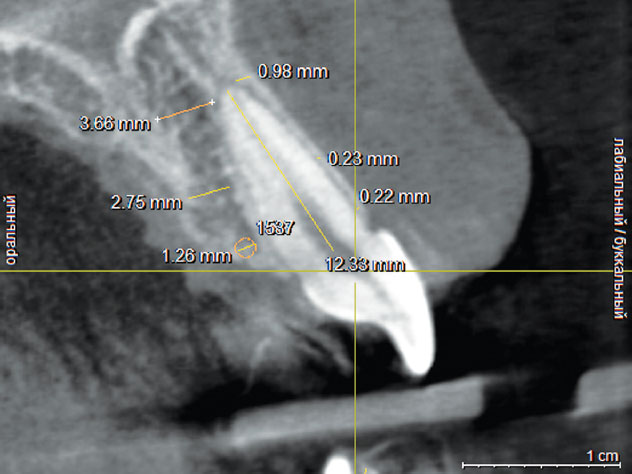

Рис. 4. Измерение плотности губчатой кости с нёбной стороны зуба 1.1

Fig. 4. Cancellous bone density measurement in the palatal part of tooth 1.1